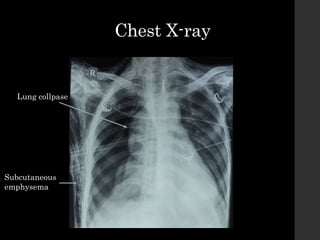

Chest X-ray

Lung collpase

Subcutaneous

emphysema